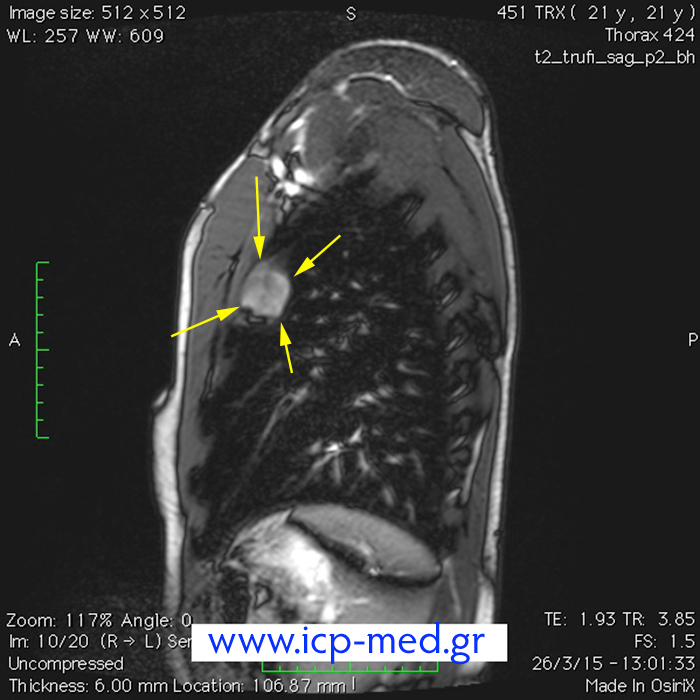

8. Προεγχειρητική MRI (οβελαία τομή)